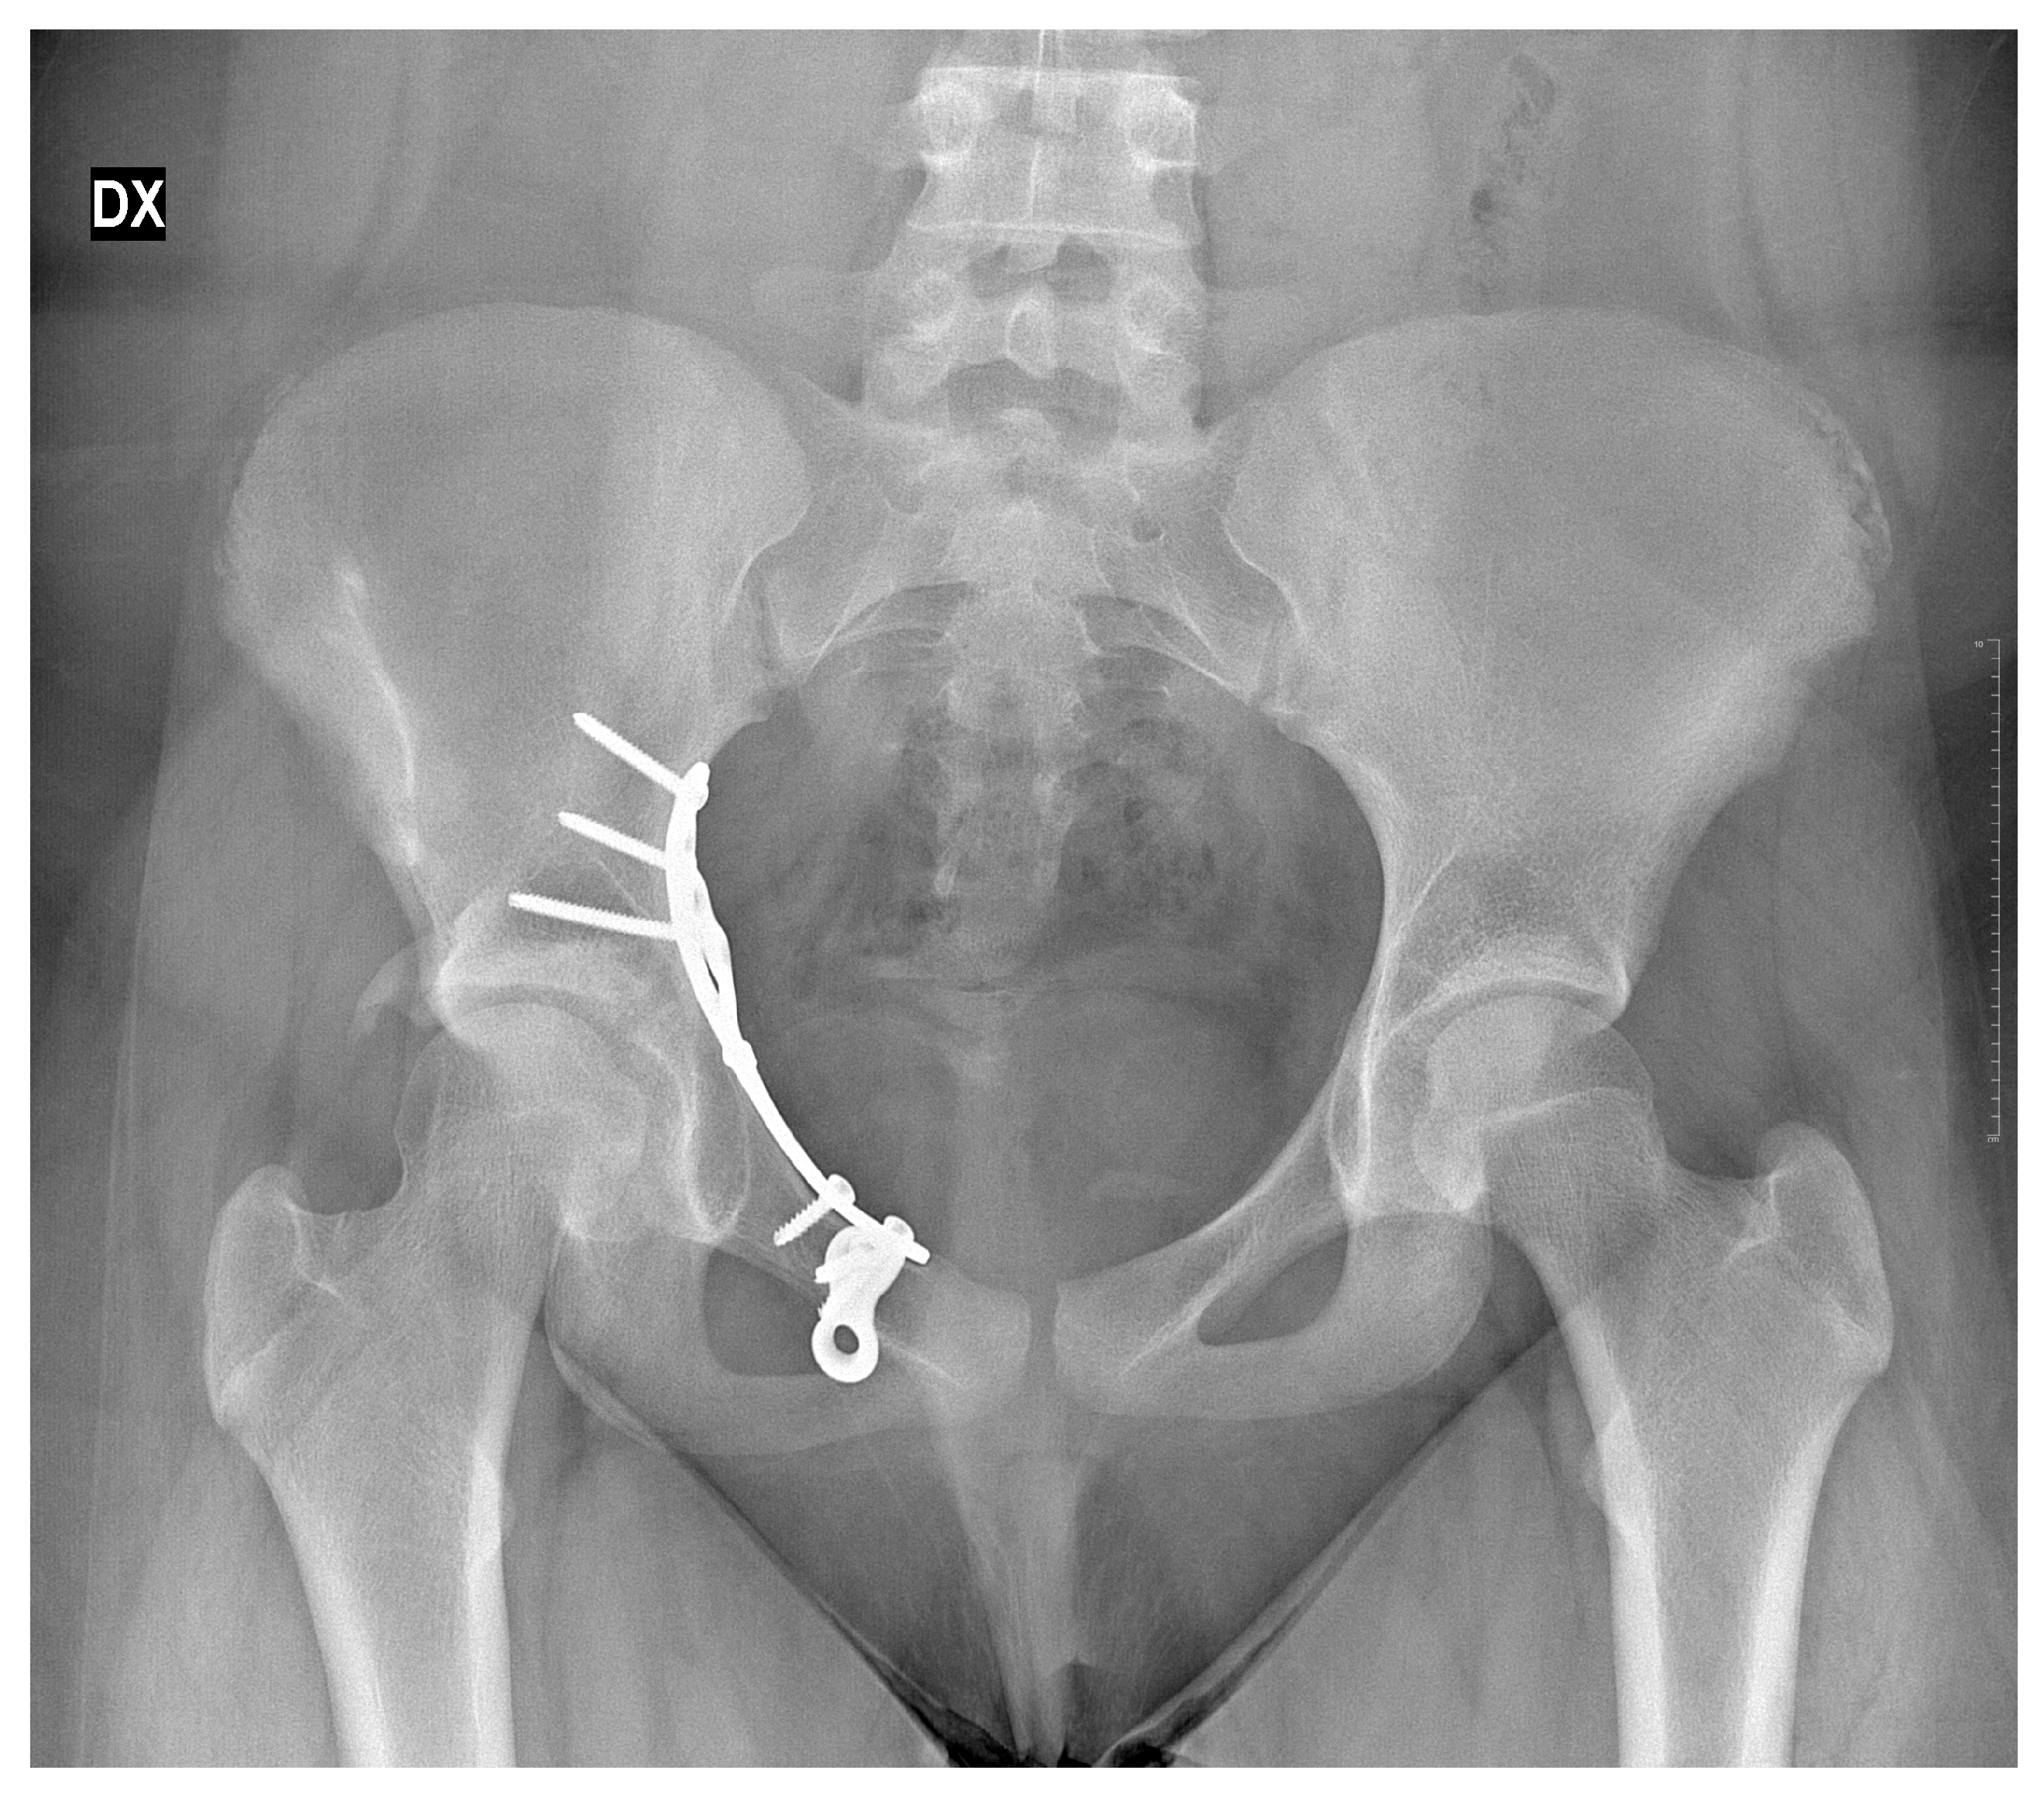

Subsequent clinical and radiographic follow-up visits were conducted at approximately 3 months, 6 months, and 4.5 years after definitive fixation hip (last X-ray was performed at 30 months follow-up). After 30 months, no further X-ray examinations were performed in order to avoid exposing the patient to unnecessary radiation for diagnostic or therapeutic purposes (Figure 5, Figure 6 and Figure 7).

Figure 7.

X-rays follow-up at 30 months by the surgical treatment. DX = Right.

Pelvic radiographs demonstrated a congruent right hip joint (at 30 months of follow-up), maintained reduction in the acetabulum with well-positioned hardware, and no evidence of premature closure of the triradiate cartilage, acetabular dysplasia, coxa magna, avascular necrosis, or degenerative joint changes. The patient was advised to pursue weight reduction and regular physical activity; further reviews were scheduled on an as-needed basis.